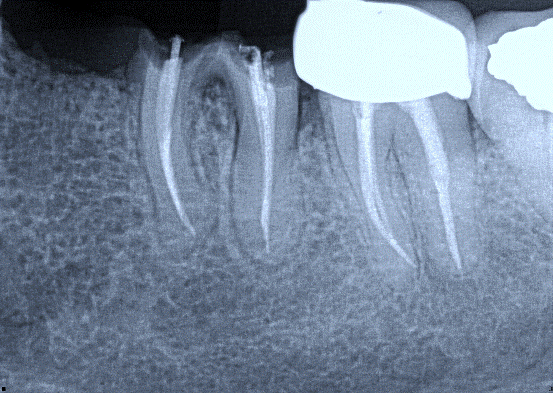

1. (Select ONE OR MORE correct answers)

Which of the following may complicate the extraction of tooth 3.5?